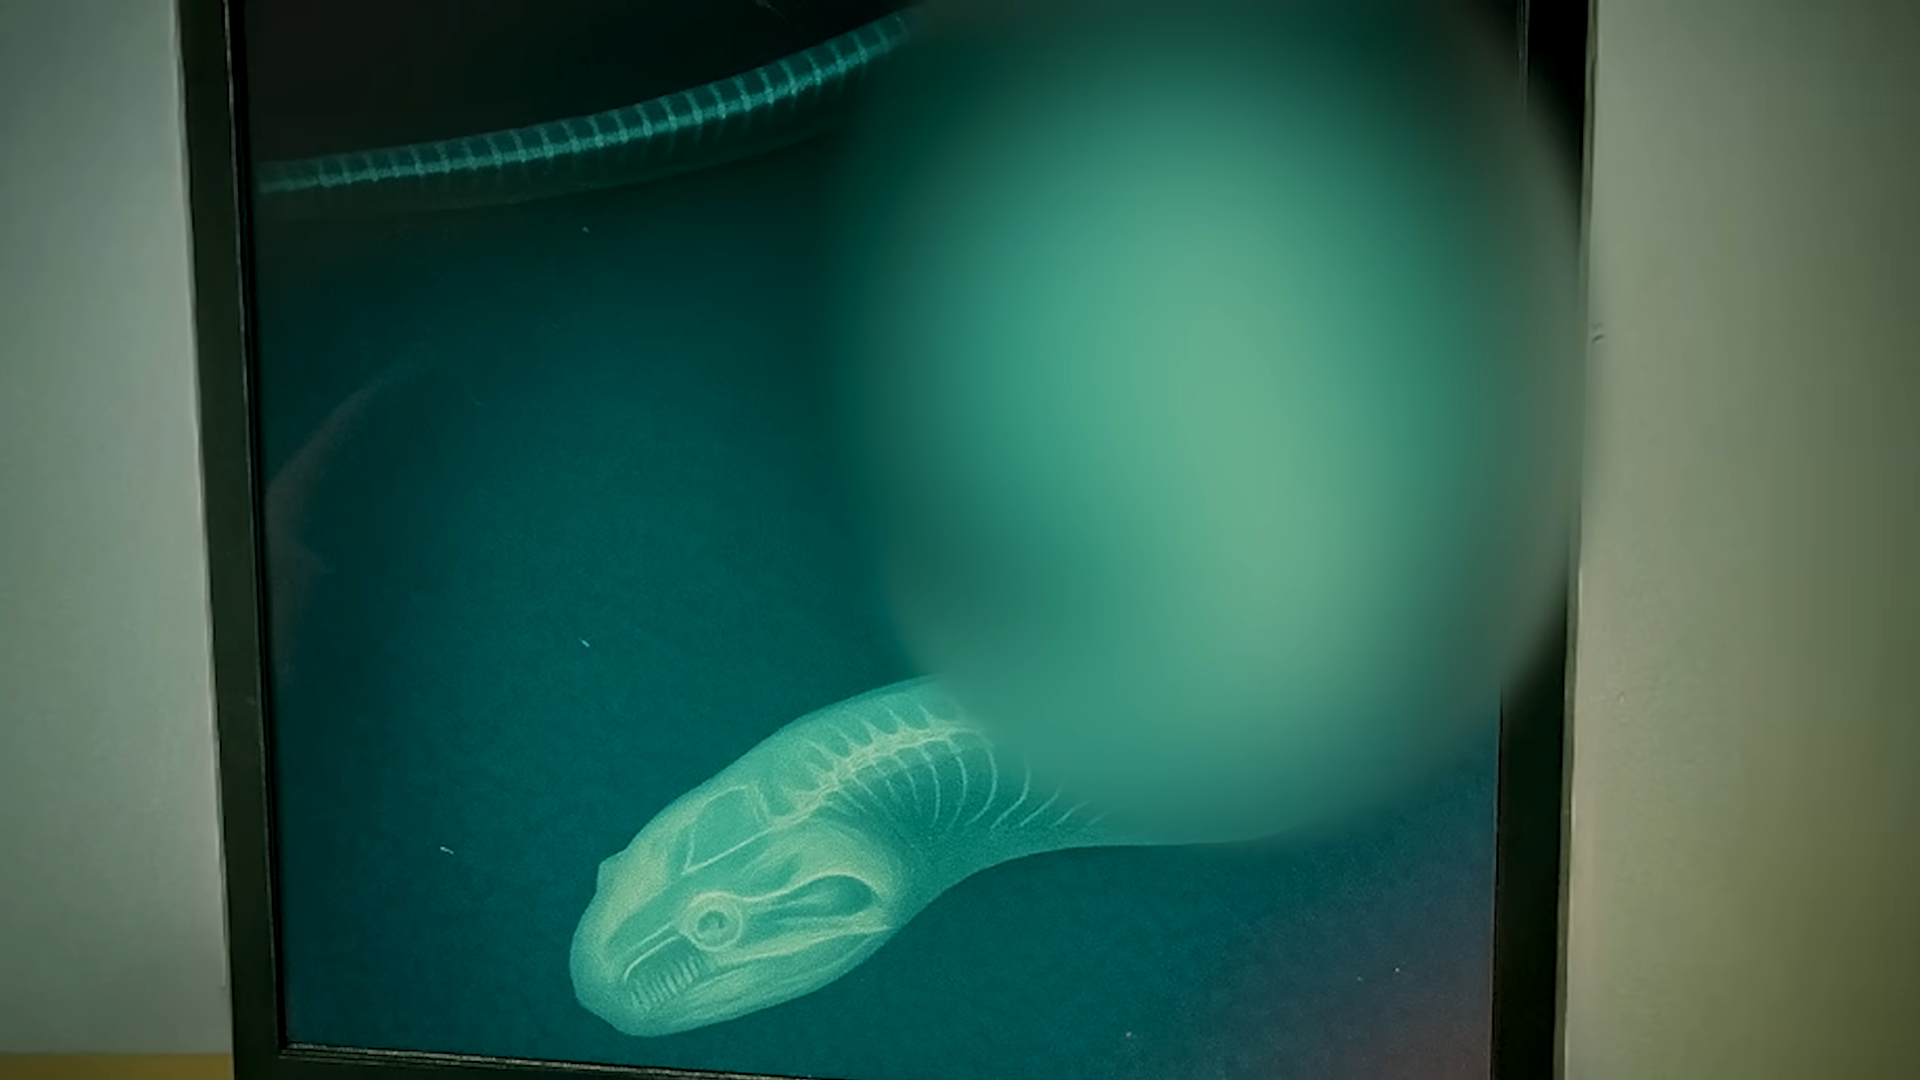

The X-Ray Revelation

In a bid to uncover the truth, the authorities decided to perform an X-ray on the snake.

The results were startling.

The X-ray revealed that the snake had ingested a foreign object, which was likely causing its refusal to eat.

This discovery raised serious questions about the zookeeper’s negligence and the overall management of the zoo.

The authorities were quick to act, leading to the zookeeper’s arrest on charges of animal cruelty.